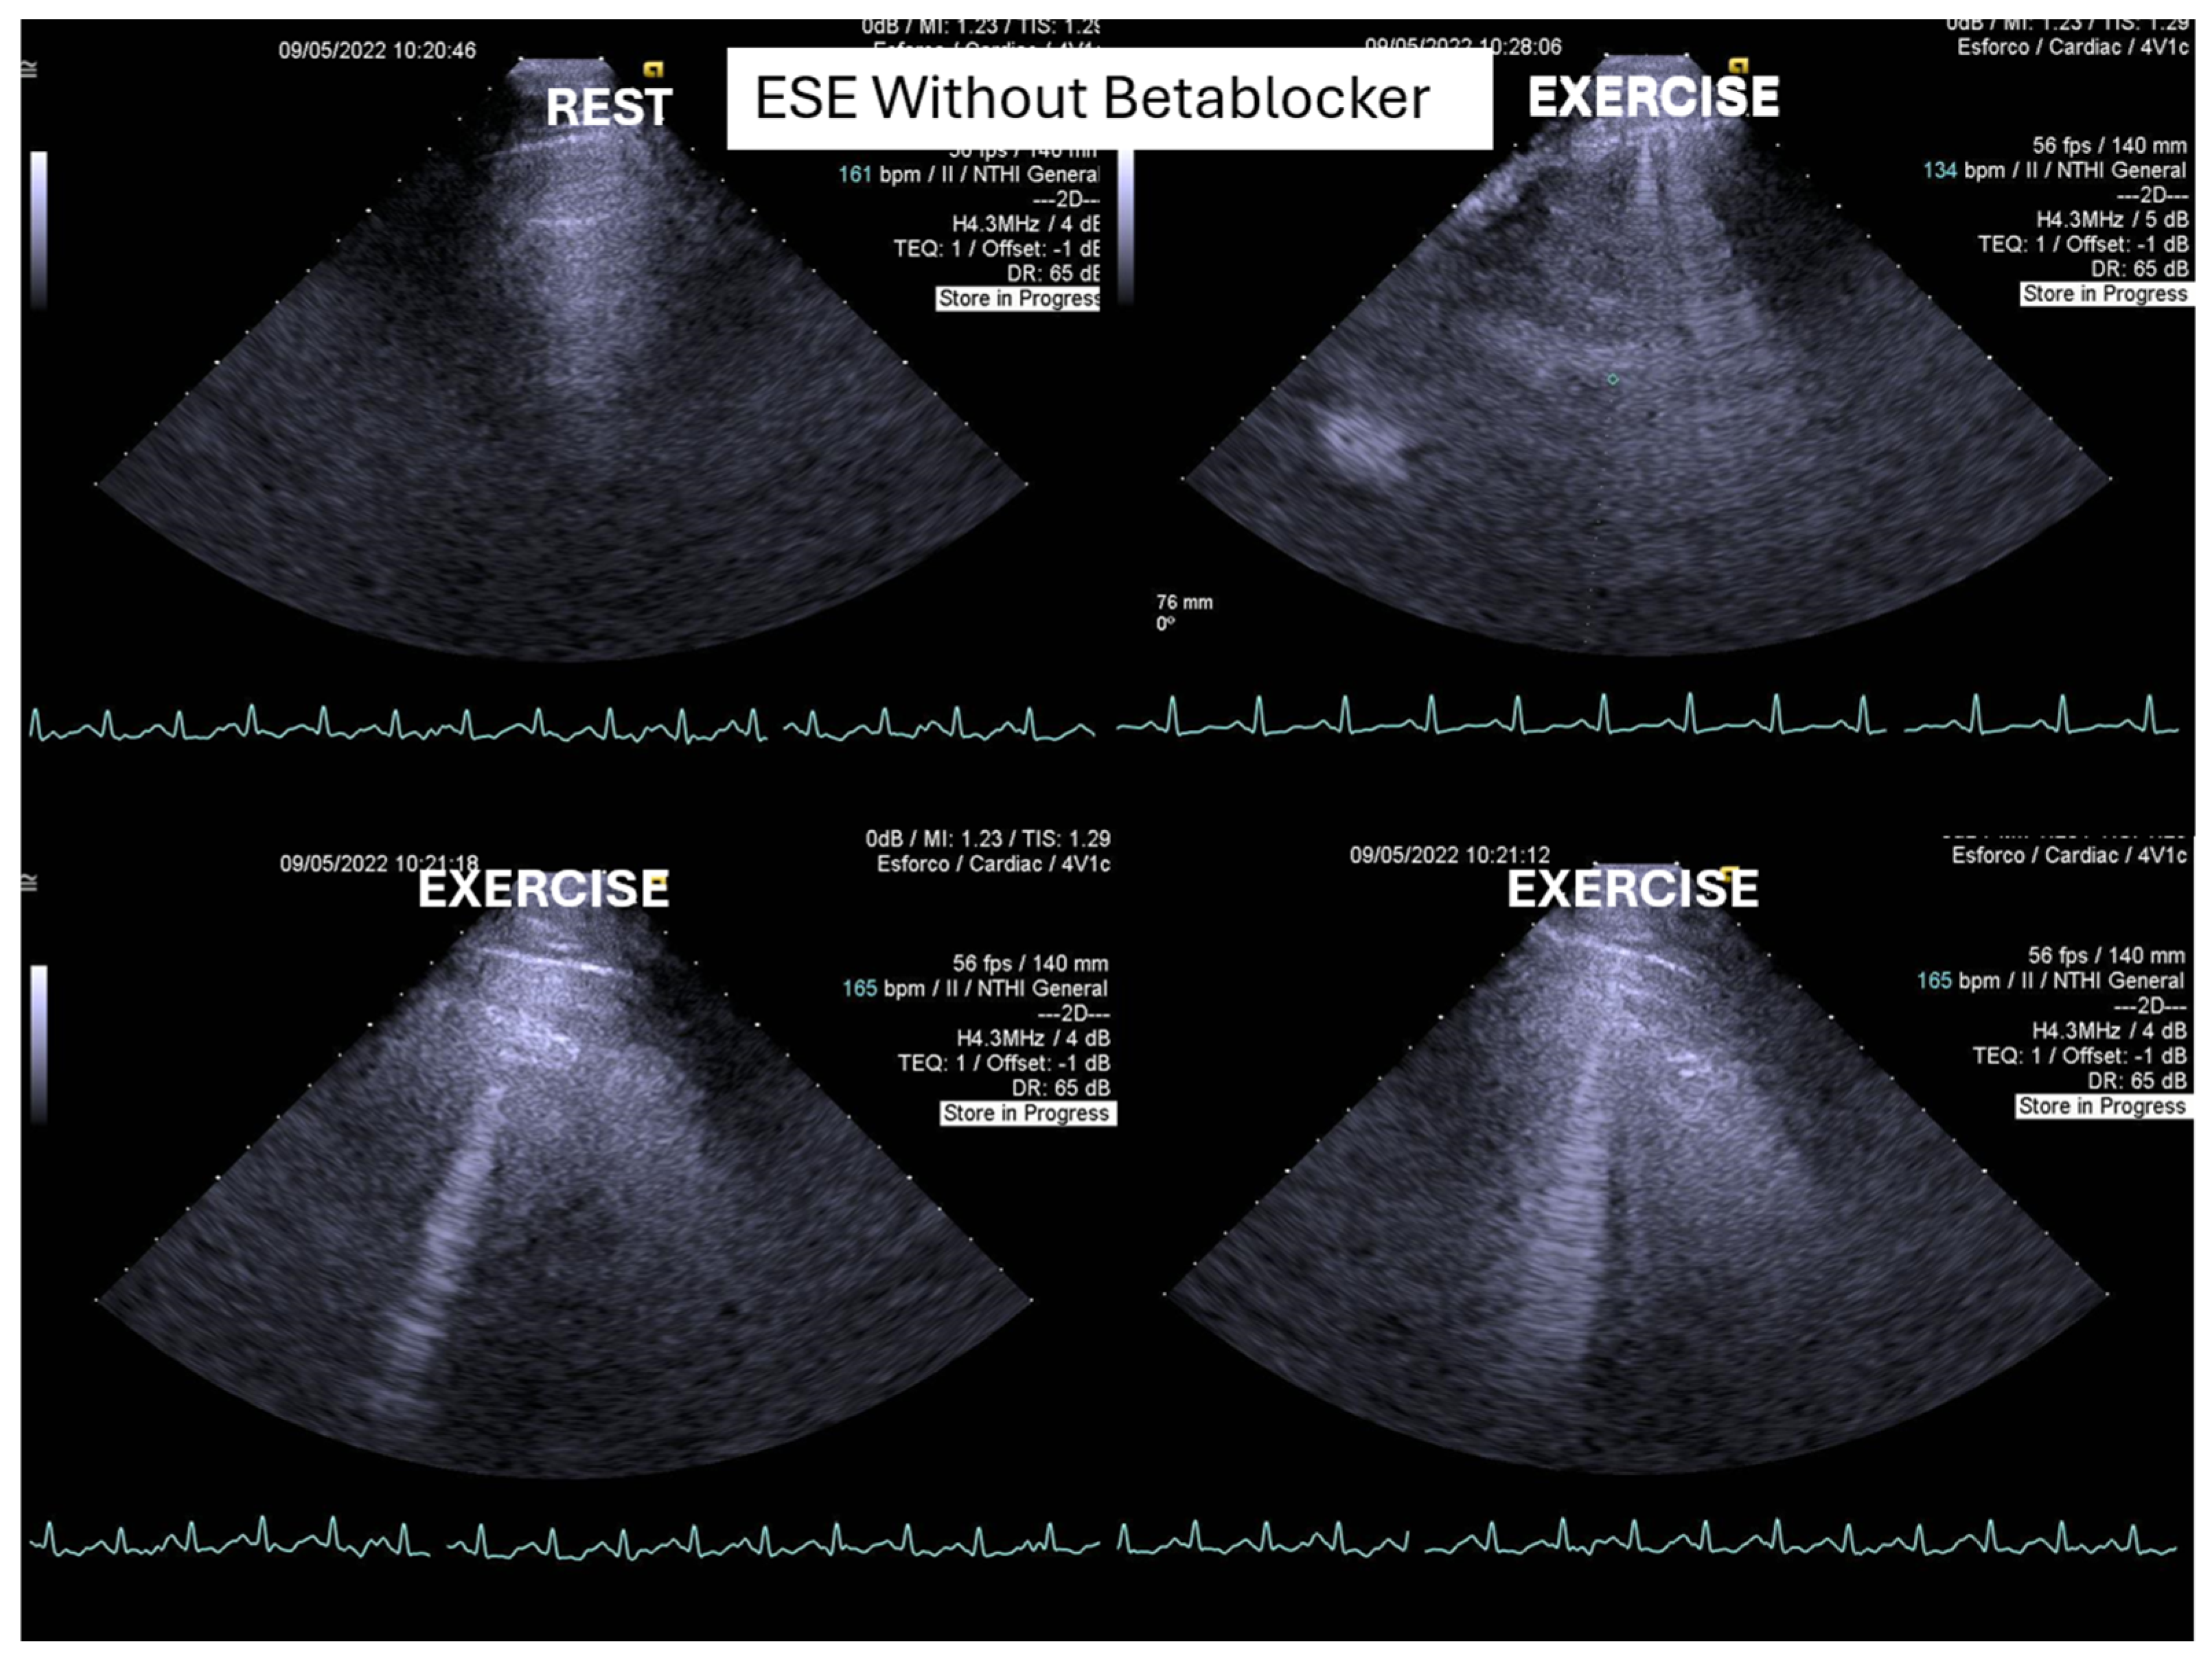

ESE’s potential extends beyond diagnosis, as it may guide targeted therapy. Our experience supports its value in initiating β-blockers in selected pediatric cases (Figure 1 and Figure 2) [1,9].

Figure 1.

This figure shows an intraventricular gradient during exercise in an adolescent experiencing exercise-related chest pain and syncope, accompanied by elevated troponin levels (top). A significant reduction in the gradient is observed under beta-blocker therapy (bottom).

On the resting echocardiogram, all the exams were considered normal with and without beta-blockers. No wall motion abnormalities were detected in any of the exams, with or without beta-blockers. In the complete group, IVPG (Figure 1) at peak exercise on the first assessment was 105 ± 38 mmHg, with mitral valve SAM in 28 adolescents (Figure 2). Among the 29 adolescents treated with beta-blockers, IVPG was 58 ± 32 mmHg, p < 0.0001.

In our study, beta-blocker therapy was associated with reductions in heart rate, exercise-induced ST-segment alterations, systolic blood pressure, and, consequently, peak heart rate–systolic blood pressure product (HR × SBP). The incidence of intraventricular gradients (IVGs) (Figure 1) and systolic anterior motion (SAM) of the mitral valve (Figure 2) during exertion also decreased significantly. These hemodynamic improvements were accompanied by a notable reduction in symptoms during exercise testing and follow-up